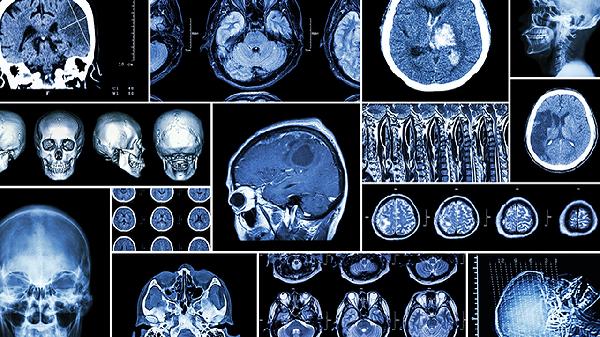

脑血管短暂性供血不足可能导致局部脑功能异常,常见于高血压或动脉硬化患者。典型表现为突发性记忆中断,持续数分钟至一小时,可能伴随言语障碍或肢体麻木。需通过脑部CT或核磁共振排除脑梗死风险,急性期可遵医嘱使用阿司匹林肠溶片、氯吡格雷等抗血小板药物。